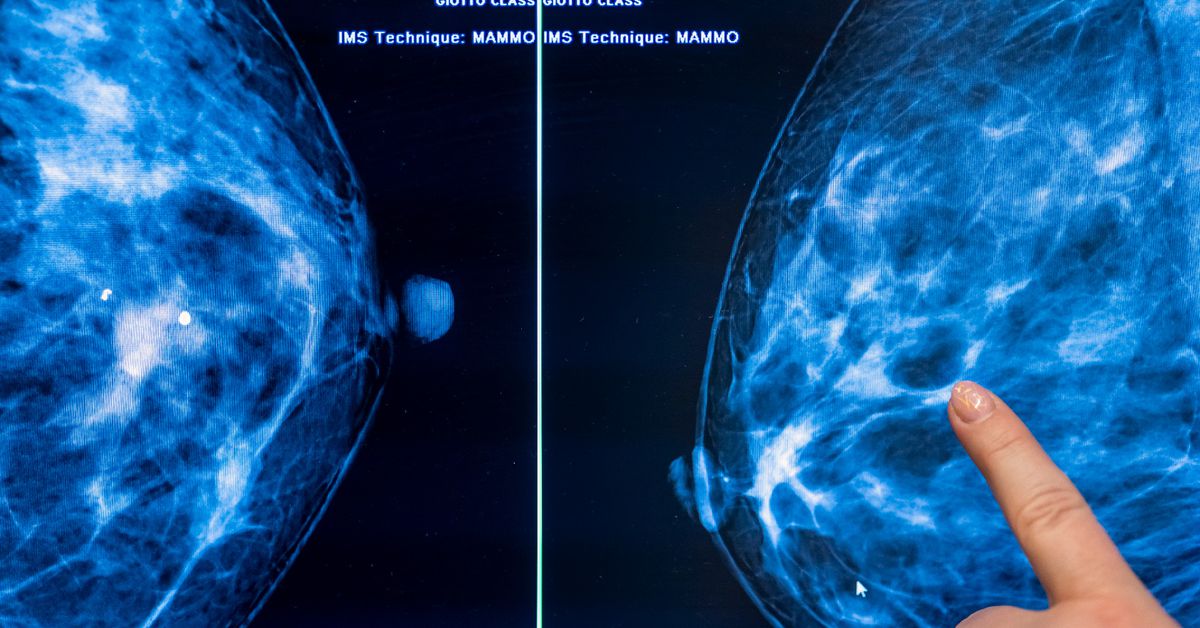

The U.S. Preventive Services Task Force, which guides cancer screening and other preventive services insurers must cover, has not met since March 2025, with July and November meetings canceled by a government shutdown and several vacancies leaving the panel short-handed. Draft recommendations, including updates to cervical cancer screening and perinatal depression, remain pending as the group typically issues 20–25 guidance items annually but published only about five last year. Critics warn that political reshaping of federal advisory panels under Health Secretary RFK Jr. could further slow evidence-based recommendations.